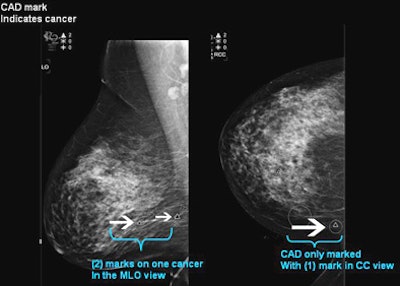

![]() |

| CAD reveals true-positive cancer with two marks on MLO view, 1 mark on CC view. All images and data courtesy of Dr. Stamatia Destounis. |

What did CAD find where? Three of the masses were detected on MLO, six at CC, and four on both projections. Among the calcifications, 60 were detected on both MLO and CC, two on CC alone, and one on MLO alone.

CAD's overall case sensitivity, i.e., the number of lesions CAD marked compared to the number of lesions visible on both views, was 87%, or 39/45 cases. CAD found four of the lesions on MLO only, eight on CC only, and 27 in both views. Thus, image sensitivity was 78% on CC views, compared to only 69% on MLO views, Destounis said.